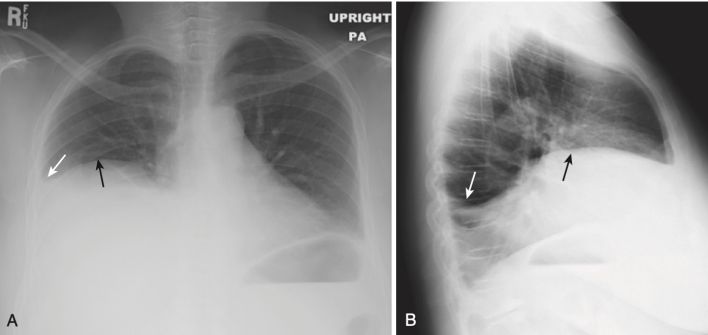

Mờ các góc sườn hoành (Blunting of the Costophrenic Angles)

Khi tràn dịch dưới phổi phát triển về kích thước, trước tiên nó sẽ lấp đầy và do đó làm mờ rãnh sườn hoành sau, có thể nhìn thấy ở phim phổi nghiêng. Điều này xảy ra với khoảng 75 mL chất dịch (Hình 4).

- Khi tràn dịch đạt đến kích thước khoảng 300 mL, nó làm mờ góc sườn hoành bên, có thể nhìn thấy trên phim X quang ngực thẳng (Hình 5).

- Cạm bẫy: Dày màng phổi do xơ hóa cũng có thể gây mờ góc sườn hoành.

- Giải pháp: Sẹo (ví dụ, do nhiễm trùng, phẫu thuật hoặc máu trong khoang màng phổi trước đó) đôi khi tạo ra hình dạng mờ kiểu dốc trượt tuyết đặc trưng, không giống như hình dạng như sụn chêm (meniscoid) của tràn dịch màng phổi (Hình 6).

- Dày màng phổi sẽ không thay đổi vị trí khi bệnh nhân thay đổi tư thế, khác với hầu hết các trường hợp tràn dịch.